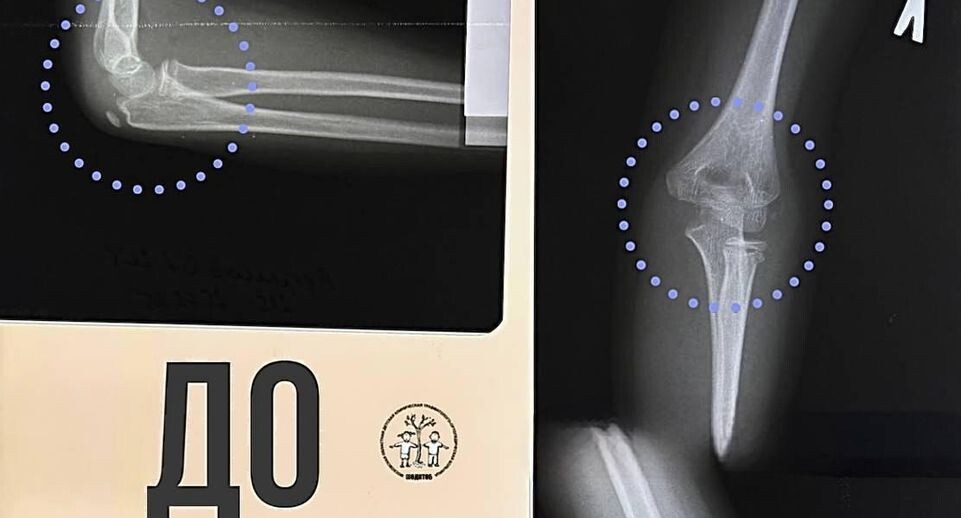

Врачи Московской областной детской клинической травматолого-ортопедической больницы помогли 11-летнему ребенку, упавшему с высоты 2,2 метра. Мальчик сломал обе руки. Специалисты провели обследование и выявили открытый перелом правого локтя, а также закрытые переломы правого плеча и левой лучевой кости. «Мы провели малоинвазивное вмешательство, в ходе которого с помощью специальных металлических спиц мы аккуратно вернули кости в правильное анатомическое положение и зафиксировали их для надежного сращения. При таких травмах процесс заживления обычно занимает больше времени, чем при изолированных переломах», — пояснила травматолог-ортопед МОДКТОБ Джамиля Кукуева. Операция прошла успешно — нервы не пострадали, а отек быстро начал спадать. Ребенка уже выписали. Позже мальчику предстоит повторная операция для удаления металлических конструкций, а также реабилитация. Автор: Елизавета Теличенко

Специалисты провели обследование и выявили открытый перелом правого локтя, а также закрытые переломы правого плеча и левой лучевой кости.

«Мы провели малоинвазивное вмешательство, в ходе которого с помощью специальных металлических спиц мы аккуратно вернули кости в правильное анатомическое положение и зафиксировали их для надежного сращения. При таких травмах процесс заживления обычно занимает больше времени, чем при изолированных переломах», — пояснила травматолог-ортопед МОДКТОБ Джамиля Кукуева.